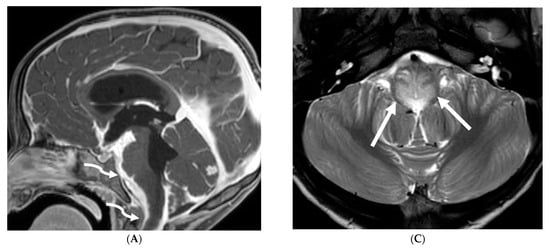

Anti-MOG antibody associated demyelination (MOGAD) frequently presents as Acute Disseminated Encephalomyelitis (ADEM) in children and opticospinal involvement in young adults [105]. Bilateral but asymmetric T2 hyperintense lesions occur in thalamus, pons and cerebellar peduncles are common in children [106]. Optic nerve involvement typically presents as a long segment with anterior predominance, in contrast to the posterior predominance seen in Neuromyelitis Optica Spectrum Disorders (NMOSD) and the short segment involvement characteristic of Multiple Sclerosis (MS) [106].

LME has been shown to present early in the disease course and is much more common in children (33%) compared to adults (8%) [107]. Gadde et al. found that 8% of pediatric MOG antibody-associated demyelination cases had only LME without any other central nervous system manifestation. LME when present can be particularly helpful in differentiating from NMOSD [106]. Furthermore, Valencia-Sanchez et al. reported a significant association between LME and cerebral cortical encephalitis in MOG antibody-associated disease. This finding suggests that LME may be an important marker for cortical involvement and potentially more severe disease (Figure 21) [108].

Figure 21.

Sagittal T2 (A,B), axial FLAIR (C), axial T2 cervical spine (D) at the level of C7 vertebral body and Axial T2 orbits (E): 12-year-old girl presented with right focal motor seizure and left temporal lobe slowing on electroencephalogram (EEG). Right eye vision loss and irritability. Ill-defined areas of signal abnormalities are identified within the RIGHT mesial temporal lobe and bilateral medulla (white arrows). FLAIR hyperintensity is identified on the left central sulcus (black arrow). Small focus of signal abnormality is seen on the right side of the cord at the 7th cervical vertebra (C7) (dashed arrow). There is also bilateral papilledema (arrowheads). Post contrast axial T1 (F,G), axial T1 orbits (H) and axial T1 cervical spine at C7 (I): Asymmetric LME (black arrows) predominantly involving the left cerebral hemisphere, with minimal right parietal involvement is seen. Ill-defined enhancement in the right mesial temporal lobe, and right greater than left medulla (white arrows) corresponds to the signal abnormality. There is right greater than left, optic nerve enhancement (curved arrow). Single small enhancing lesion in the spinal cord on the right at the level of C7 corresponds to the signal abnormality (dashed arrow). Features favor a demyelinating process. MOG antibodies were positive at 1:20 in keeping with Myelin oligodendrocyte glycoprotein (MOG) antibody disease (MOGAD).